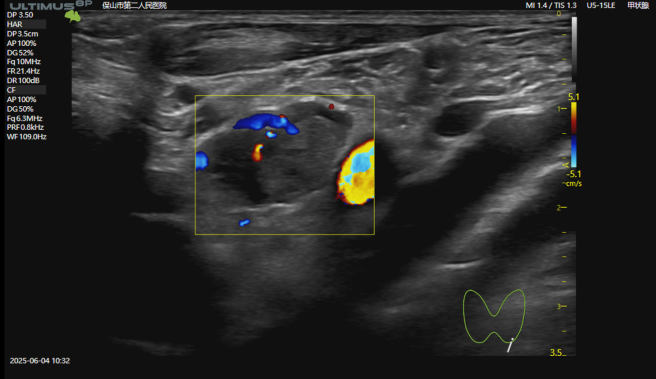

甲状旁腺结节—考虑腺瘤

术前造影

结节明显强化